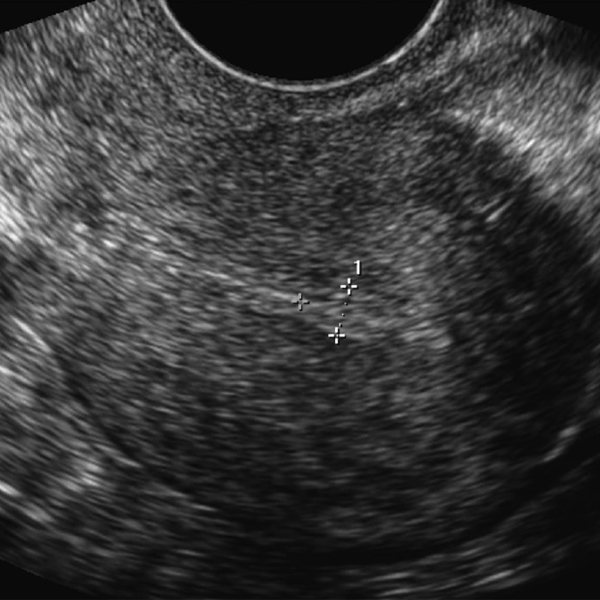

Frozen Embryo Transfer Baseline Ultrasound . This is a critical step as it allows for a thorough evaluation of the reproductive organs. With regard to the transfer of fresh embryos in eight rcts and four cohort studies, transabdominal (ta) ultrasound—guided embryo transfer was found to improve. A frozen embryo transfer (fet) cycle is a process to help you become pregnant. Fet uses embryos (fertilized eggs) that have been frozen. Recent randomized controlled trials have shown that implantation and pregnancy rates were improved with ultrasound. If the ultrasound looks normal and your. The ivf process takes about 2 weeks to complete. A baseline ultrasound allows us to evaluate the ovaries and pelvic organs to determine if it is an appropriate time to begin ovarian stimulation, which is the first phase of ivf. It varies depending on your response to medications. The first thing to do is to undergo a transvaginal ultrasound scan. For your ivf cycle, you will either do a fresh embryo transfer or you will freeze all of your embryos and your transfer will be scheduled for the next month, known as a frozen embryo transfer (fet).

FET Cycle Baseline Ultrasound! // Frozen Embryo Transfer 2 YouTube Frozen Embryo Transfer Baseline Ultrasound For your ivf cycle, you will either do a fresh embryo transfer or you will freeze all of your embryos and your transfer will be scheduled for the next month, known as a frozen embryo transfer (fet). The first thing to do is to undergo a transvaginal ultrasound scan. It varies depending on your response to medications. If the ultrasound. Frozen Embryo Transfer Baseline Ultrasound.

Frozen Embryo Transfer Round 2 Baseline Appointment YouTube Frozen Embryo Transfer Baseline Ultrasound This is a critical step as it allows for a thorough evaluation of the reproductive organs. The first thing to do is to undergo a transvaginal ultrasound scan. Recent randomized controlled trials have shown that implantation and pregnancy rates were improved with ultrasound. With regard to the transfer of fresh embryos in eight rcts and four cohort studies, transabdominal (ta). Frozen Embryo Transfer Baseline Ultrasound.

Frozen embryo transfer baseline check / IVF FET 4 / Transfer on Frozen Embryo Transfer Baseline Ultrasound The first thing to do is to undergo a transvaginal ultrasound scan. A baseline ultrasound allows us to evaluate the ovaries and pelvic organs to determine if it is an appropriate time to begin ovarian stimulation, which is the first phase of ivf. If the ultrasound looks normal and your. For your ivf cycle, you will either do a fresh. Frozen Embryo Transfer Baseline Ultrasound.